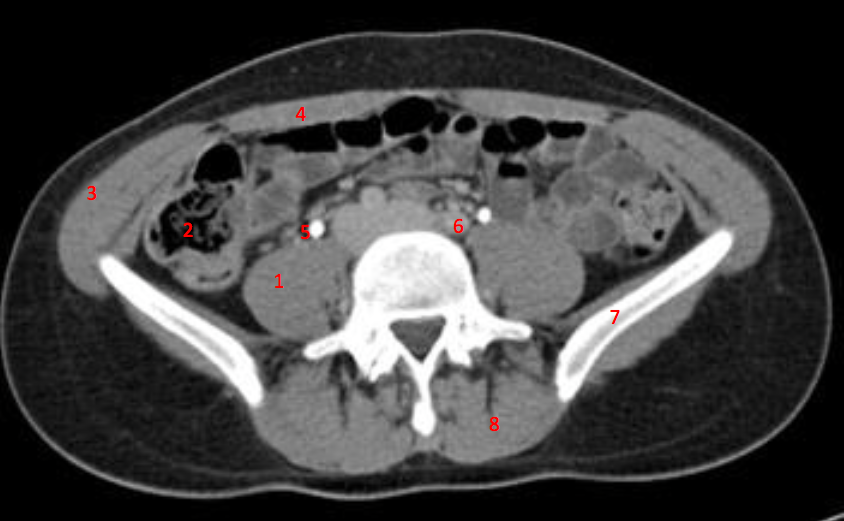

3

Number 1?

R kidney

16

Number 2?

IVC

17

Number 4?

Rt lobe liver

21

Number 5?

Rt ureter

22

Number 6?

Descending colon

23

Number 9?

Superior mesenteric artery

24

Number 8?

25

Number 7?

Abdominal aorta

26

Rt erector spinae muscle

39

Spleen

40

Lt iliac blade/ilium

43

Rt oblique muscle

44

Rt rectus abdonimalis muscle

45

Rt psoas muscle

50

Ascending colon

51

Rt gluteus muscle

55

Caecum